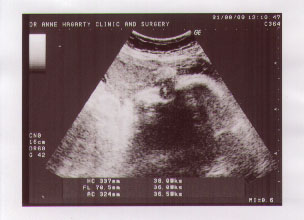

| It looks like this one is going to be a thumb sucker. |